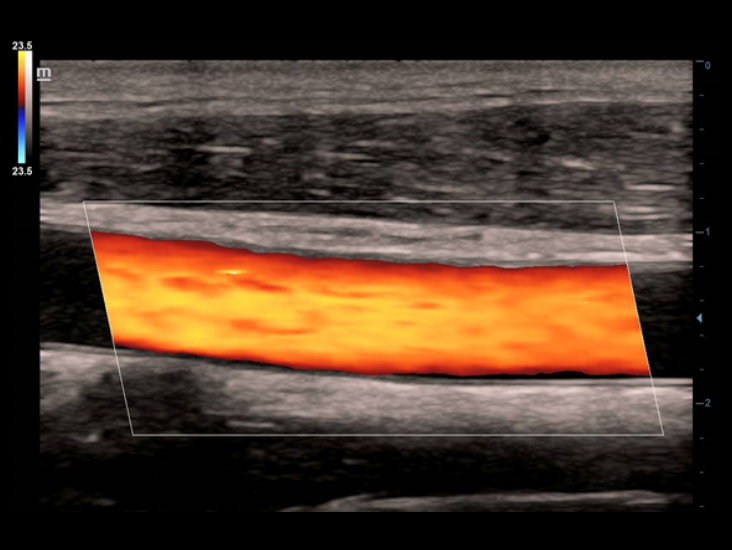

Transductores ComboWave

En comparaciĂłn con los sensores tradicionales, los transductores ComboWave utilizan un nuevo tipo de material piezoelĂ©ctrico compuesto que optimiza notablemente el espectro acĂșstico y reduce la impedancia acĂșstica. AdemĂĄs de integrarse con la tecnologĂa Ășnica 3T de Mindray, los transductores lineales ComboWave ofrecen un rendimiento sobresaliente con una gran resoluciĂłn de imagen y uniformidad en ecografĂas vasculares, de tiroides, de mama, etc.

Smart Track

Smart Track proporciona una optimizaciĂłn rĂĄpida e inteligente de imĂĄgenes vasculares con un sencillo manejo de un solo toque. Puede optimizar el espectro de Color, Potencia y PW mediante seguimiento automĂĄtico y reducir pasos que llevan tiempo. Por lo tanto, el flujo de trabajo del examen vascular se simplifica con una Ăłptima visualizaciĂłn.